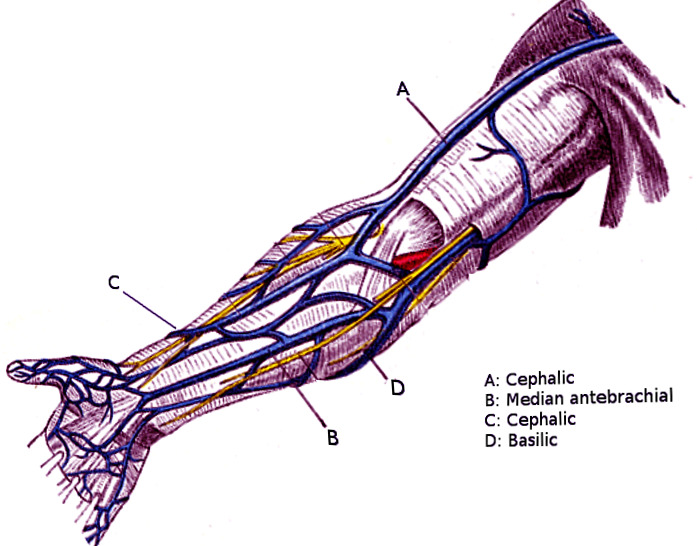

Veins Arm Hi-res Stock Photography And Images - Alamy

veins arm illustration vector alamy stock major high